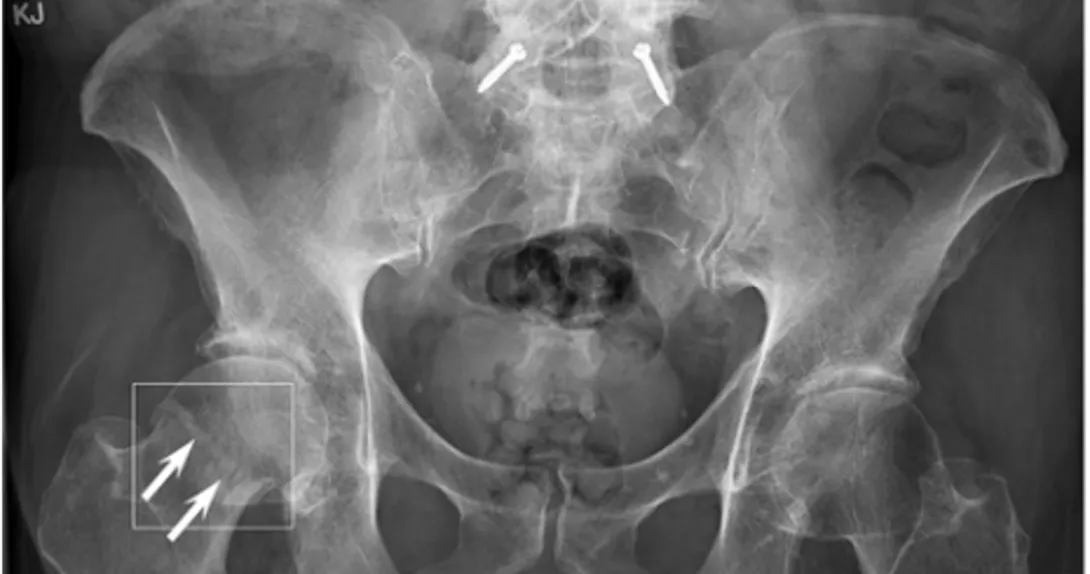

BoneView uses artificial intelligence to detect potential fractures and sends results to radiologists for confirmation. The software received a CE mark in Europe in March 2020.